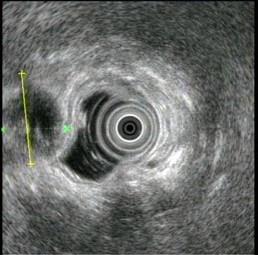

问题 患者,38岁,进食后常有上腹不适多年,1个月前发作一次右上腹剧痛,无腹膜炎体征,超声内镜如图中,胆囊病变可能的诊断是 ( )

选项 A.胆囊积脓 B.胆囊腺肌病 C.胆囊癌 D.胆囊多发息肉 E.胆囊多发结石

答案 E